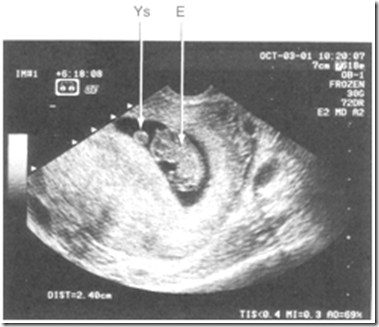

image

Kehamilan intrauterine 8 minggu. Terlihat gambaran embrio (E) dan yolk sac (YS)